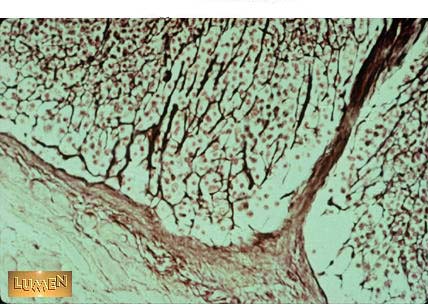

Reticular fibers become more pronounced with what kind of stain?

Silver